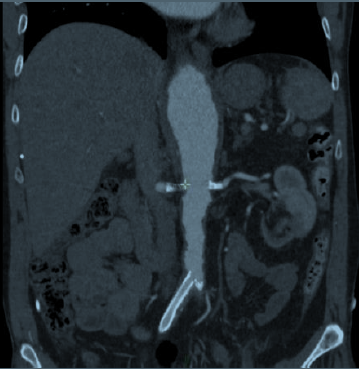

Interventions aortiques et des troncs digestifs